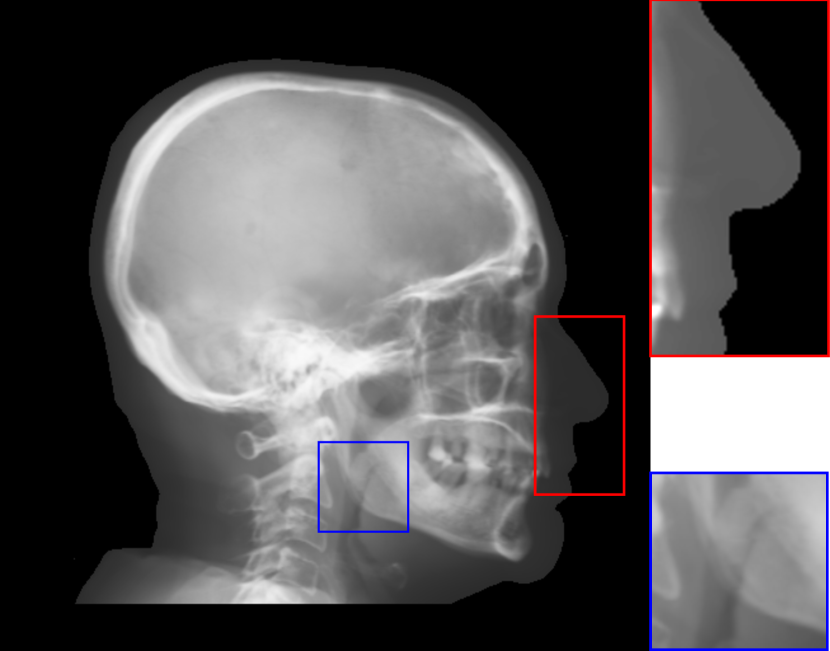

Fig. 8: Synthetic cephalogram examples from 3D CBCT volumes with different methods. (a)-(d) are comparison results while (e)-(h) are the (intermediate) results of our proposed method: (a) RayCast using orthogonal projection; (b) RayCast using perspective projection; (c) MIP using the largest 100 pixels along each orthogonal ray; (d) CycleGAN using patches from (a) and ISBI real conventional cephalograms; (e) RayCast using orthogonal projection from the skeleton enhanced volume; (f) original sigmoid transform of (e) using Eqn. (4) with air background recovery; (g) modified sigmoid transform of (e) using Eqn. (6), the final Type I synthetic cephalogram using orthogonal projection; (h) the final Type I synthetic cephalogram using perspective projection. The nose ROIs are redisplayed in the intensity window [0, 125] for better visualization. The mandible angle ROIs are for the visualization of the difference between orthogonal projection and perspective projection. The perceptual index of each synthetic cephalogram is displayed in the corresponding subcaption.

The synthetic cephalograms generated by different methods are displayed in Fig. 8. Figs. 8(a) and (b) show the cephalograms synthesized by the orthogonal [33] and perspective [21] RayCast methods, respectively, which are the most widely used methods for cephalogram synthesis from CBCT volumes. Comparing Fig. 8(b) to Fig. 8(a), due to different magnification factors of structures at different positions in perspective projection, anatomical structures on both sides of the midsaggital plane cannot overlap well, for example, the projections of the left and right mandible (gonial) angles in the zoom-in ROI in Fig. 8(b). In Figs. 8(a) and (b), the skeleton structures, soft tissues and airways are well observed. However, the image contrast in these two synthetic cephalograms are different from conventional cephalograms (Fig. 2(a)). The cephalogram synthesized by MIP using the largest 100 pixels along each orthogonal ray is displayed in Fig. 8(c). In this subfigure, skeleton structures are well observed since they have high intensity. Nevertheless, low intensity structures, e.g. the throat airway, might disappear. The CycleGAN [59] synthetic cephalogram is shown in Fig. 8(d). Compared with the conventional cephalogram example in Fig. 2(a), it has the closest image contrast. Hence, it achieves the best perceptual index of 5.53. However, some detailed anatomical structures are incorrect. For example, the nose has extremely low intensity in the zoom-in ROI. It also suffers from geometric distortion. As a consequence, the stitching artifacts are visible.

Figure 8(e)-(g) are the Type I synthetic cephalograms of different steps using orthogonal projection. Fig. 8(e) is the orthogonal RayCast celphalogram synthesized from the enhanced CBCT volume using Eqn. (1). Compared with Fig. 8(a), skeleton structures in Fig. 8(e) have higher contrast. Fig. 8(f) is obtained by applying the original sigmoid transform in Eqn. (4) to Fig. 8(e), where the skeleton structures are further enhanced. Moreover, the appearance of Fig. 8(f) is very close to conventional cephalograms. However, the soft tissues like the nose and lips have an almost constant intensity value, as displayed in the zoom-in ROI in Fig 8(f). The final Type I synthetic cephalogram with orthogonal projection is displayed in Fig. 8(g). With the proposed modified sigmoid transform in Eqn. (6), the contrast in the soft tissues is brought back, as displayed in the zoom-in ROI. For comparison, the final Type I synthetic cephalogram with perspective projection is displayed in Fig. 8(h). Compared with Fig. 8(g), the mandible angles in the zoom-in ROI of Fig. 8(h) are not overlapped well due to perspective magnification.